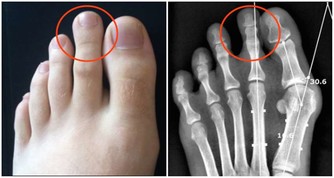

比如,睾丸癌是罕見的,但在40歲以下的男性中最常見。如果他抱怨陰囊疼痛無力或感覺沉重,應該檢查一下。事實上,所有40歲以下的男性都應該進行睾丸檢查。